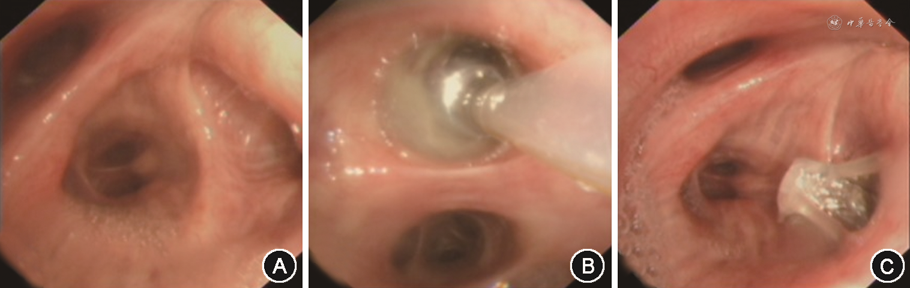

2.手术流程:(1)寻找漏点:通过数字引流瓶来判断漏点。首先使用球囊导管封堵支气管,在数字屏幕上的流量数值明显下降,逐步趋近于零,提示该支气管为漏气责任支气管。同时,使用Chartis系统来检测肺叶之间的侧支通气,也可以辅助寻找漏点。如果球囊远端没有侧支通气来供应气道,来自肺叶的气流会逐渐减少,连续流量的读数可判断目标瓣区是否存在侧支通气[13];如果球囊导管置入漏气责任支气管,则出现持续性负压。数字胸腔引流系统和Chartis系统同步使用,可增加漏点的检出率。测漏的顺序是从叶支气管到段、亚段支气管,每个部位重复3次,部分患者同时存在多个漏点,需要加以识别。(2)活瓣置入:在找到漏点后,先要测量责任支气管的直径,以选择合适尺寸的活瓣置入。具体步骤为:活瓣输送导管前端有一个十字状软翼,将软翼置于目标支气管内,让软翼充分张开,确保支气管直径小于长标记,但大于短标记,如不然,则换另一尺寸的输送导管再次测量或选择下一级支气管测量,见图3。使用系统提供的活瓣释放器将活瓣压缩到输送导管的远端。输送导管经支气管镜工作通道引导至目标气道。安装到位后,活瓣膨胀[9],在放置活瓣后观察胸腔闭式引流瓶,若封堵成功,则漏气量明显减少,见图4。活瓣置入的数量根据漏点的个数以及侧支通气的情况来决定,原则上尽量少地置入活瓣以达到较好的封堵效果。活瓣置入的顺序根据置入角度与尺寸由难到易的选择。

3.术后评估:术后每月复查支气管镜,观察活瓣留置情况,清理分泌物直至封堵成功。术后2周复查胸部CT评估治疗效果,如影像学提示气胸完全吸收并顺利拔管则判定封堵成功。胸管拔除后3个月可取出活瓣,见图4。